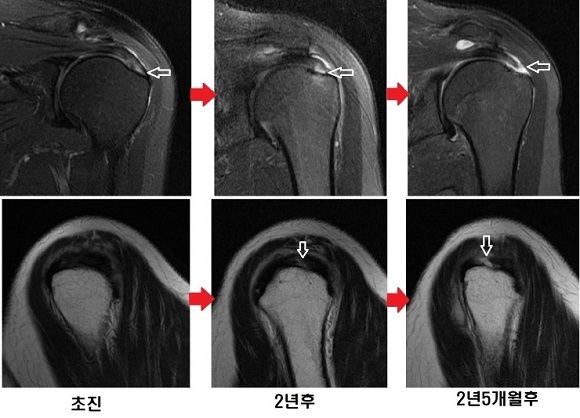

▲ 어깨 회전 근개 손상 과정

질환도 초기라면 주사치료나 체외충격파치료와 같은 비수술적 치료로도 증상이 호전될 수 있다. 하지만 치료받지 않고 방치할 경우 손상을 넘어 파열로

이어질 수 있으며, 한번 파열된 힘줄은 자연적인 치유가 어렵다. 불필요한 수술적 치료는 피해야 하지만 어깨회전근개 힘줄파열은 파열의 크기에 따라

완치율에도 영향을 미치는 만큼 적기에 수술적 치료가 필요하다.